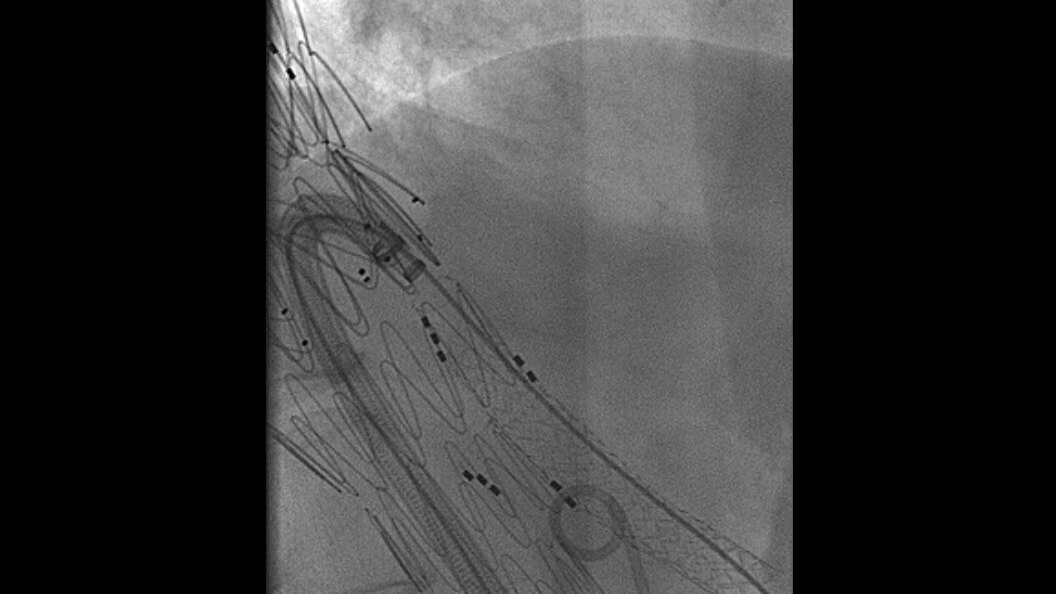

Embo ASSIST AI

Embo ASSIST1 with Virtual Injection, is a 3D Visualization software solution designed to help clinicians simulate injections dynamically and thus perform embolization procedures with confidence.